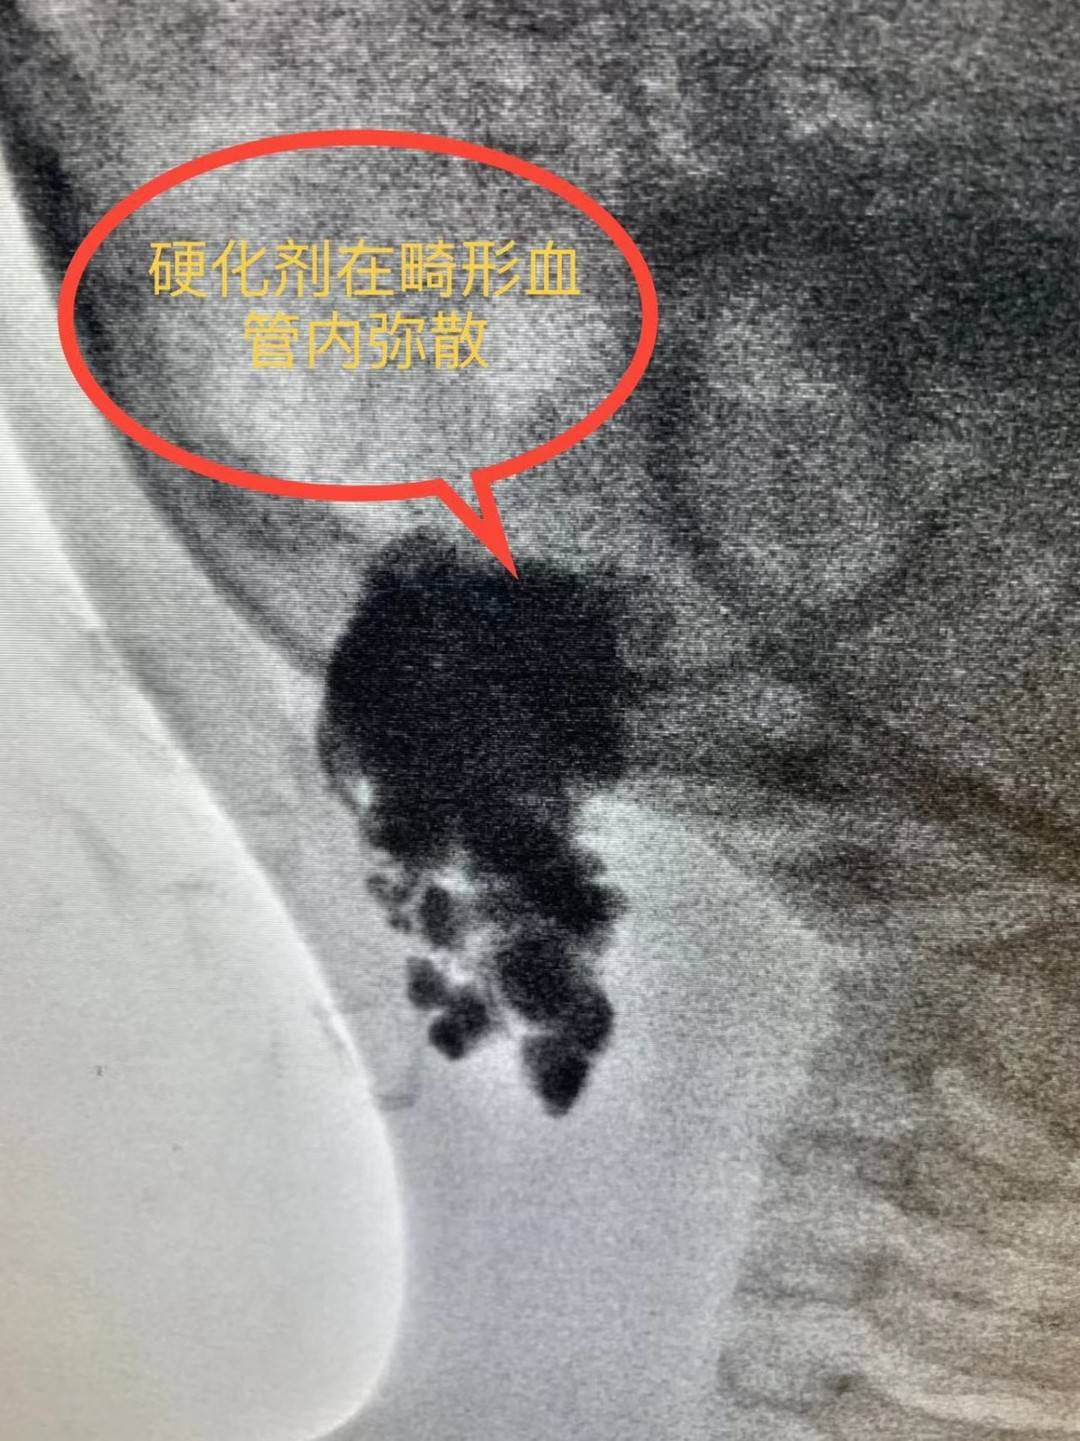

“血管畸形介入硬化治疗即血管畸形经皮硬化术。

需要在医学设备的引导下,用一根细针穿刺到病灶内部注入硬化剂,使整个病灶内都充满硬化剂,不留死角。药物将血管内皮细胞破坏,纤维化闭塞畸形血管管腔,很快使其慢慢萎缩,逐渐被机体吸收。”李炯介绍说,早期的血管畸形经系统的硬化治疗后,只需1个月即可完全恢复正常,较大的肿块3—4个月也可完全消除。